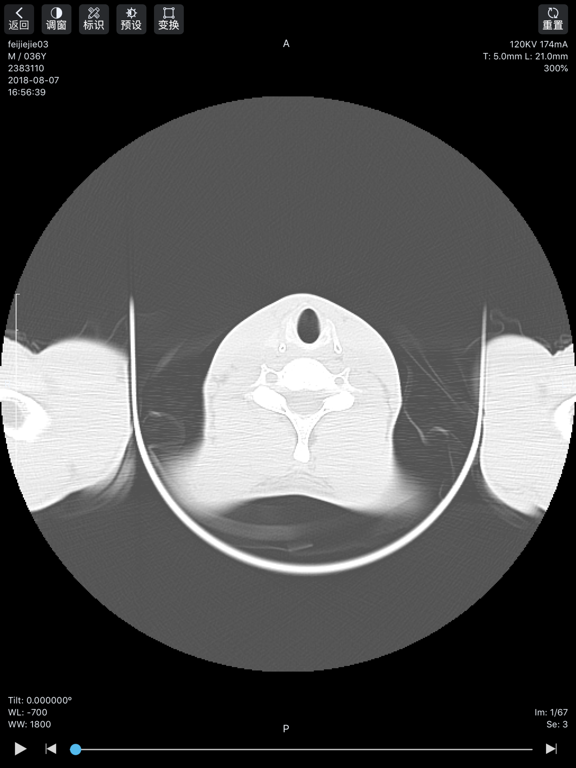

飞图影像App是飞图影像云平台的移动端应用,医生通过此应用,可实现以下功能: - 移动办公——随时随地调阅影像数据,无论在院内还是院外,都可阅片、写报告; - 医疗协作——疑难病例发起协助请求,请求上级医生或专家予以协助,远程诊断; - 交流研讨——与其他医生分享病例,进行专业研讨和学术交流,提升专业技能。 技术特性: - 原始数据,高清影像——DICOM格式,信息细节全保存,精度更高; - 多项功能,强大实用——可实现WL、测量、角度、CT值、旋转等操作; - 使用简便,快速上手——符合医生使用习惯,无需过多繁琐学习过程; - 秒传秒开,顺滑流畅——领先的GPU计算、影像预加载、影像本地保存等技术,拒绝卡顿、模糊、加载等待时间过长; - 多重措施,确保安全——严格审核,二次验证,防止数据被恶意应用;加密传输,防止信息外泄。1.优化APP性能 2.优化UI 3.新增若干功能

软件截图